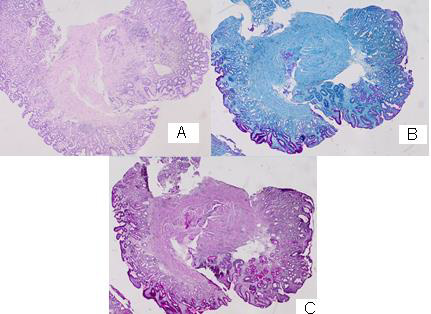

CT with venous contrast, mediastinal and pulmonary window

Double-sided pleural effusions, larger left, with some compression on the ninth and tenth segment of the left lower lung lob. A parenchyma solid contrast-amplifying lesion, most likely metastatic, is visualized peripherally in the fourth segment to the left, close to the chest wall. Mediastinal lymphadenopathy (Figure 1/А); Pulmonary CT scan after 1 month - slightly increased pleural effusion on the left, as well as parenchymal pulmonary lesion on the left associated with the chest wall (Figure 1/B).

Figure 1: CT with venous contrast, mediastinal and pulmonary window: A/double-sided pleural effusions, larger left, with some compression on the ninth and tenth segment of the left lower lung lob. A parenchyma solid contrast-amplifying lesion is visualized peripherally in the fourth segment to the left, close to the chest wall. Mediastinal lymphadenopathy. B/ Pulmonary CT scan after 1 month without substantial dynamics.